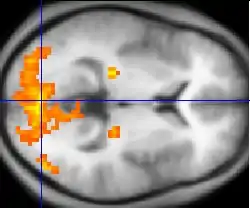

During visual search experiments the posterior parietal cortex has elicited much activation during functional magnetic resonance imaging (fMRI) and electroencephalography (EEG) experiments for inefficient conjunction search, which has also been confirmed through lesion studies. Patients with lesions to the posterior parietal cortex show low accuracy and very slow reaction times during a conjunction search task but have intact feature search remaining to the ipsilesional (the same side of the body as the lesion) side of space.[40][41][42][43] Ashbridge, Walsh, and Cowey in (1997)[44] demonstrated that during the application of transcranial magnetic stimulation (TMS) to the right parietal cortex, conjunction search was impaired by 100 milliseconds after stimulus onset. This was not found during feature search. Nobre, Coull, Walsh and Frith (2003)[45] identified using functional magnetic resonance imaging (fMRI) that the intraparietal sulcus located in the superior parietal cortex was activated specifically to feature search and the binding of individual perceptual features as opposed to conjunction search. Conversely, the authors further identify that for conjunction search, the superior parietal lobe and the right angular gyrus elicit bilaterally during fMRI experiments.

In contrast, Leonards, Sunaert, Vam Hecke and Orban (2000)[46] identified that significant activation is seen during fMRI experiments in the superior frontal sulcus primarily for conjunction search. This research hypothesises that activation in this region may in fact reflect working memory for holding and maintaining stimulus information in mind in order to identify the target. Furthermore, significant frontal activation including the ventrolateral prefrontal cortex bilaterally and the right dorsolateral prefrontal cortex were seen during positron emission tomography for attentional spatial representations during visual search.[47] The same regions associated with spatial attention in the parietal cortex coincide with the regions associated with feature search. Furthermore, the frontal eye field (FEF) located bilaterally in the prefrontal cortex, plays a critical role in saccadic eye movements and the control of visual attention.[48][49][50]